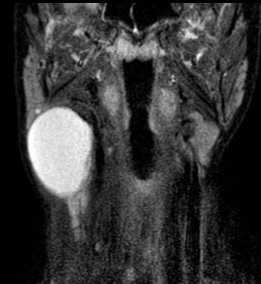

В заднем шейном пространстве встречаются нейрогенные опухоли, лифомы, липомы, лимфангиомы ( кистозные гигромы). Такие образование наилучшим обоазом видны на корональных МРТ, особенно с подавлением жира. Раличить липому и лимфангиому позволяет подавление сигнала от жира.

МРТ мягких тканей шеи. Т2-зависимый корональный срез. Лимфангиома.